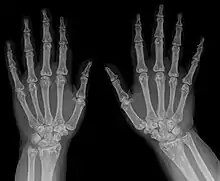

Osteopoikilosis results in multiple enostoses.

An enostosis is a small area of compact bone within the cancellous bone.[1][2] They are commonly seen as an incidental finding on radiographs or CT scans. They are typically very small and do not cause any symptoms.[3] Their radiodensity is generally similar to cortical bone.[4] No treatment is necessary. Multiple enostoses are present in osteopoikilosis.[5]